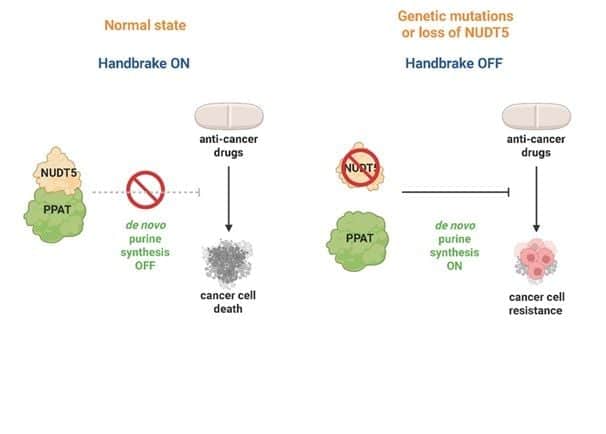

Discovery reveals ‘handbrake’ that controls cancer drug response

A world-first discovery, published in the journal Science, rewrites our understanding of how cells control the production of DNA’s…